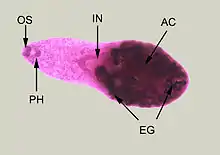

Adult specimen stained with carmine

Minute teardrop-shaped flukes found in the small intestines of fish-eating birds and mammals. The eggs are hard to tell apart from other related species so there is no accurate estimate of human infection. H. heterophyes is a small trematode, ranging up to 1.4mm long and 0.5mm wide.[4] It is covered with scale-like spikes and those spikes can range from 50–62.[9] Their pharynx is completely developed and connected to the cecum of the small intestines. Their sucker (mouth) is covered with spikes and its covering the genital opening. This means, they share one hole for eating and reproduction. Their testes is located at the posterior of the parasite and the testes are side by side.[4] The ovaries are located in the medial of the parasite, right above the testes.[4] The ventral sucker also known as the acetabulum is located at the ventral of the parasite.[4] The ventral sucker helps them attach to the host. Morphology can change depending on what fish it lives on.